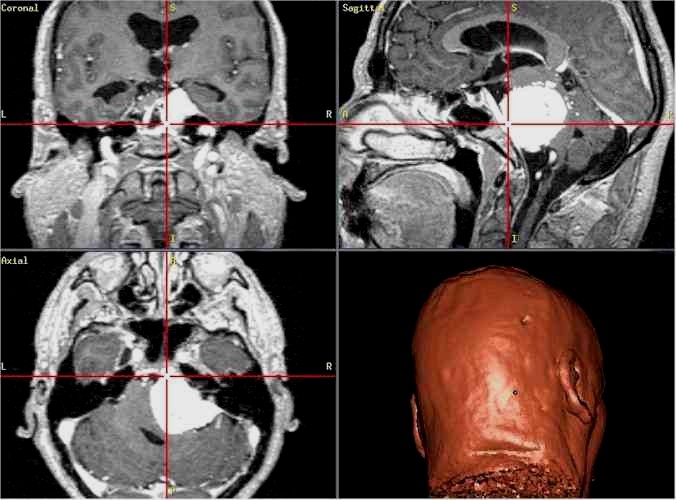

La neuronavigazione comprende sistemi computerizzati avanzati che consentono al chirurgo di conoscere in ogni momento l’esatta posizione dei propri strumenti durante l’intervento chirurgico, permettendo oggi di raggiungere praticamente qualsiasi sede intracranica mediante approcci spesso innovativi e meno invasivi.

Questi sistemi svolgono a tutti gli effetti anche una funzione stereotassica, poiché consentono di localizzare un bersaglio intracranico all’interno di un sistema di coordinate tridimensionali derivato dalle immagini di Risonanza Magnetica o Tomografia Computerizzata, con un’elevata accuratezza spaziale. In tal senso, la neuronavigazione può essere considerata una

stereotassia frameless, che non richiede l’applicazione di un casco stereotassico rigido, garantendo maggiore flessibilità e comfort per il paziente.

Cavernoma

profondo

Glioblastoma

in area critica

Il procedimento ha inizio con l’esecuzione di una Risonanza Magnetica (RM) o di una Tomografia Computerizzata (TC) del paziente, effettuate mediante protocolli di acquisizione dedicati.

Al momento dell’intervento chirurgico, il capo del paziente viene registrato nello spazio tridimensionale del computer tramite un sistema di localizzazione, generalmente ottico a infrarossi, che riconosce specifici punti di repere applicati al capo o al sistema di fissaggio.

Il computer provvede quindi a sovrapporre l’anatomia reale del paziente alle immagini RM o TC precedentemente acquisite. Durante l’intervento, il chirurgo utilizza strumenti chirurgici dotati di marker che vengono continuamente rilevati dallo stesso sistema ottico a infrarossi; in questo modo il neuronavigatore è in grado di indicare in tempo reale, sulle immagini RM o TC, l’esatta posizione degli strumenti all’interno del campo operatorio.

Grazie a questa tecnologia, l’intervento viene accuratamente pianificato alla consolle del computer, anche nei giorni precedenti l’atto chirurgico, consentendo di valutare in modo approfondito il percorso di accesso più sicuro e riducendo significativamente il rischio di dover effettuare scelte intraoperatorie non sufficientemente ponderate.

Per raggiungere una determinata sede, anche se profonda o localizzata in aree critiche, è possibile adottare traiettorie talvolta più lunghe ma che attraversano regioni cerebrali a minore rischio funzionale per il paziente. In questo modo sono venuti meno molti dei limiti legati alla difficoltà di accesso anatomico (lesioni profonde, sedi eloquenti), che in passato spesso precludevano un trattamento chirurgico.